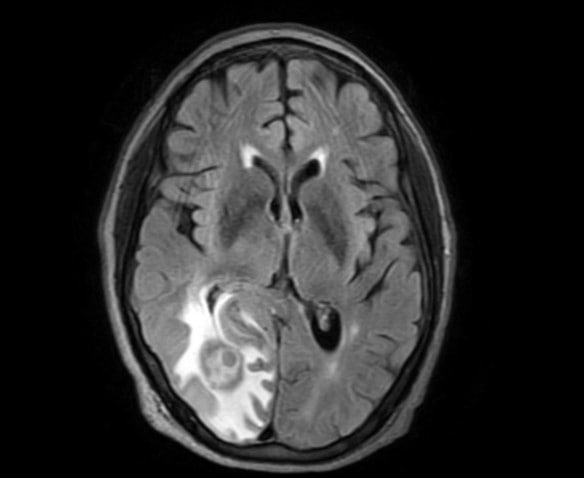

The patient underwent stat laboratory testing and neuroimaging. Laboratory testing showed decreased red blood cells, hemoglobin and hematocrit consistent with anemia, an elevated erythromycin sedimentation rate, an elevated creatinine level and reduced glomerular filtration rate consistent with kidney disease. Magnetic resonance imaging of the brain was notable for a right occipital lobe mass without herniation or hydrocephalus with a separate lesion in the left temporal horn without mass effect (Figure 2). Computed tomography scans of the brain also revealed a two-to-three-millimeter left midline shift. Computed tomography scans of the abdomen, pelvis and chest were unremarkable. Neurology was consulted and determined that a biopsy of the cranial mass was warranted to determine its pathology.

Figure 2. Magnetic resonance imaging shows a hyperreflective mass in the right occipital lobe which was biopsied to reveal a primary central nervous system lymphoma.